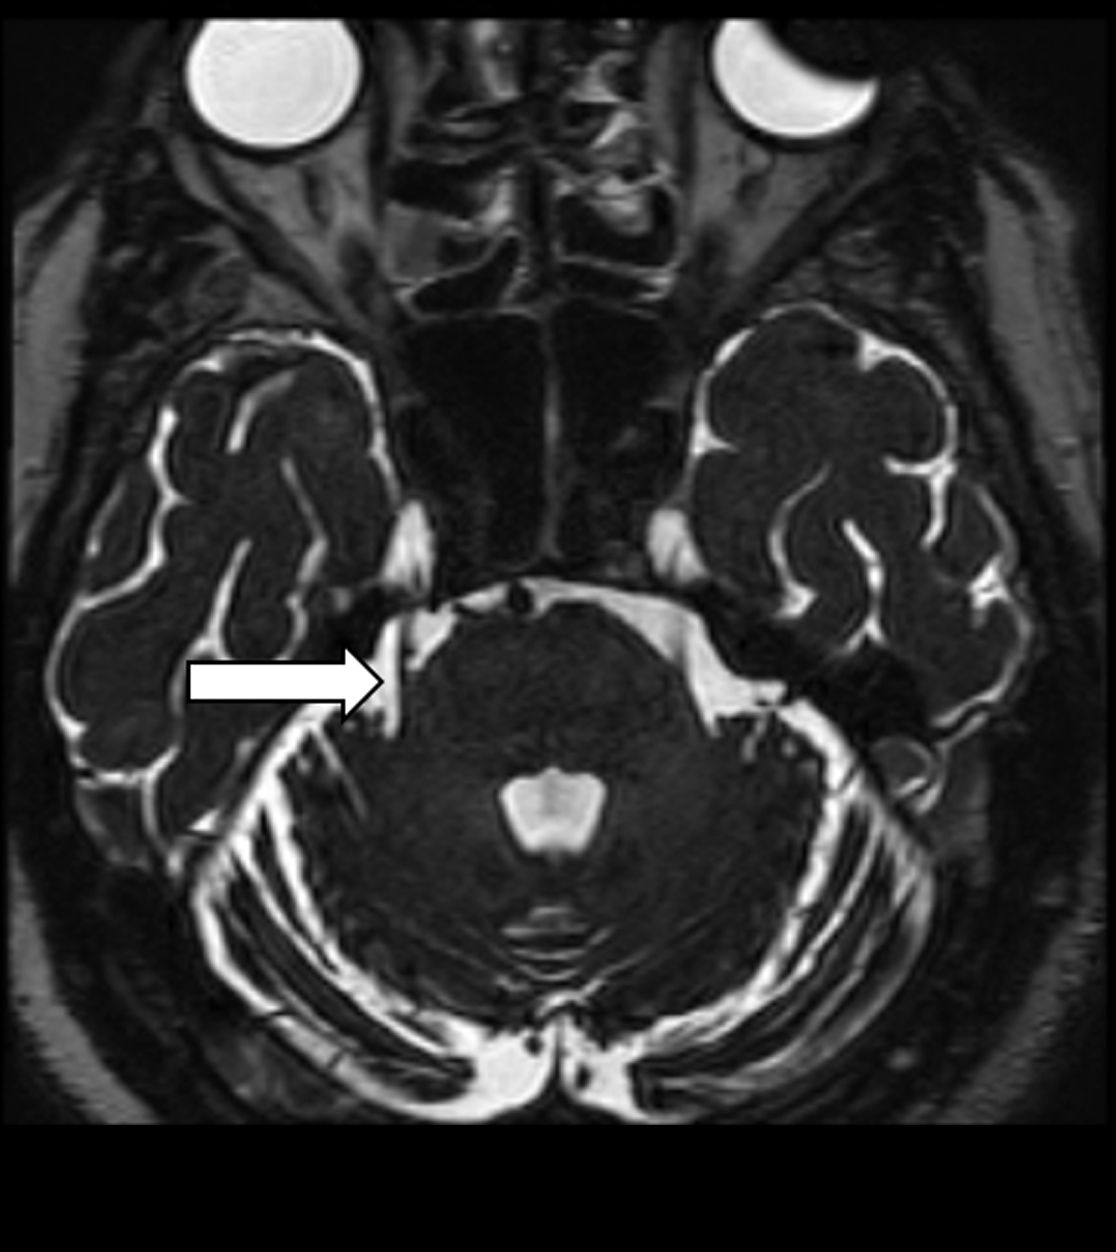

Gefäß-Nerven-Kontakt im Bereich des Nervus trigeminus (Pfeil)